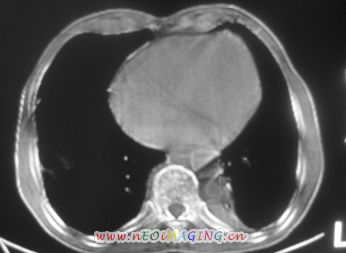

以下是引用卜一在2007-10-7 9:38:00的发言:[br]左下肺胸膜下团片影,内见含气支气管像,临近胸膜未见增厚。多考虑:1 左下肺炎症,建议消炎后复查!2 不除外肺隔离症合并感染!